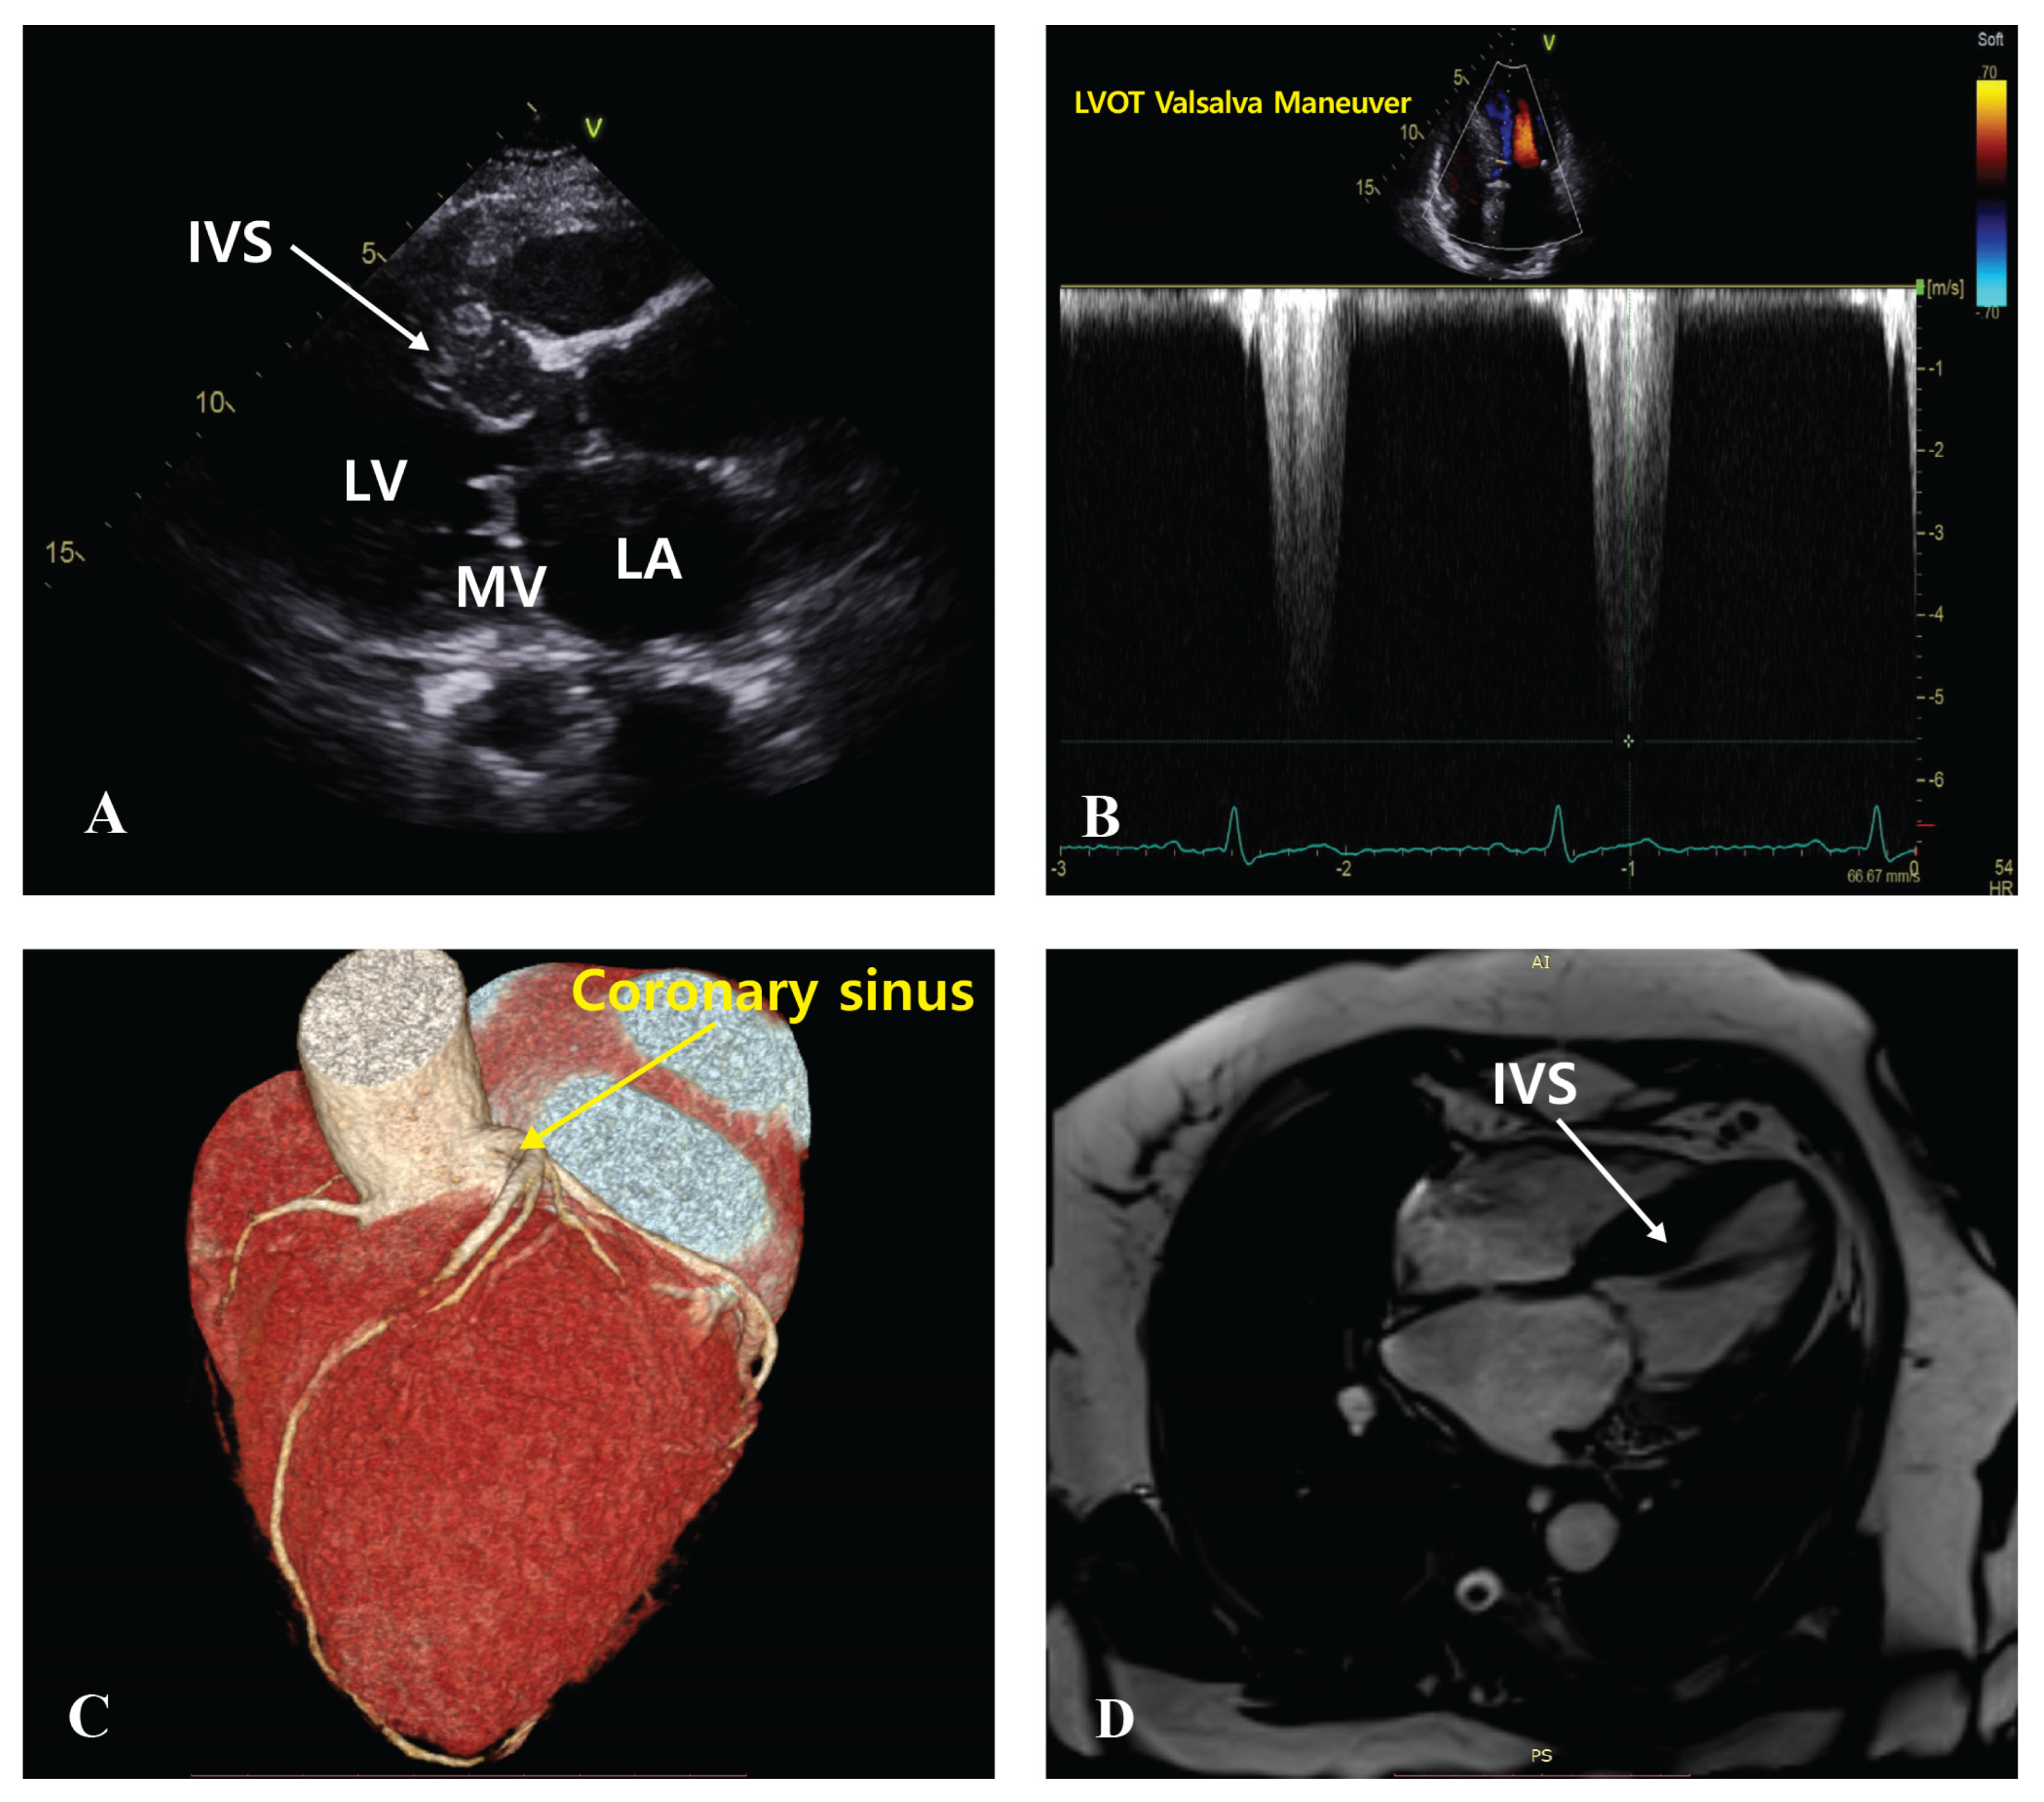

2.3. Procedure